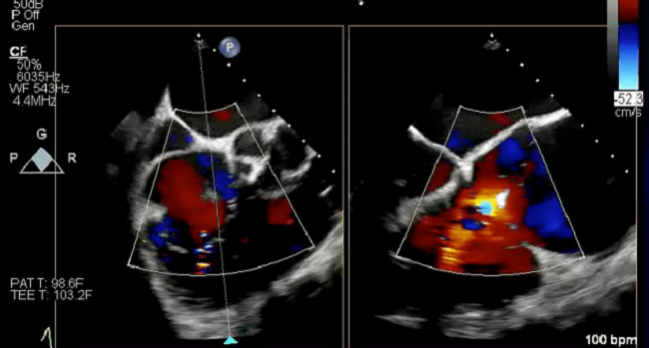

Photo Credit: Bae R. Step-by-step tricuspid clipping: echo and intervention working together. TCT 2018. September 28, 2019. San Francisco, CA.